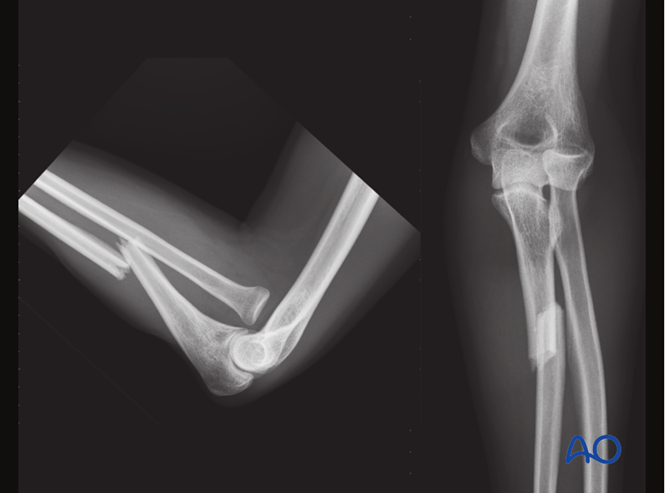

孟氏骨折脱位

●孟氏骨折脱位是指尺骨骨折合并桡骨头脱位。

●大多数情况下,桡骨头向前或向外侧脱位,向后脱位罕见。

●对于孟氏骨折脱位,必须对尺骨进行解剖复位和稳定固定,以确保桡骨头能稳定复位。

X线检查●应按照当地诊疗规范进行随访X线检查。建议在2周时进行X线检查,确保桡骨头位置保持良好,之后在6周、12周和1年时检查,评估尺骨愈合情况。●若X线显示尺骨愈合进展满意,约术后8周可开始负重。●该病例展示了孟氏骨折术前和术后的X线影像。

术前